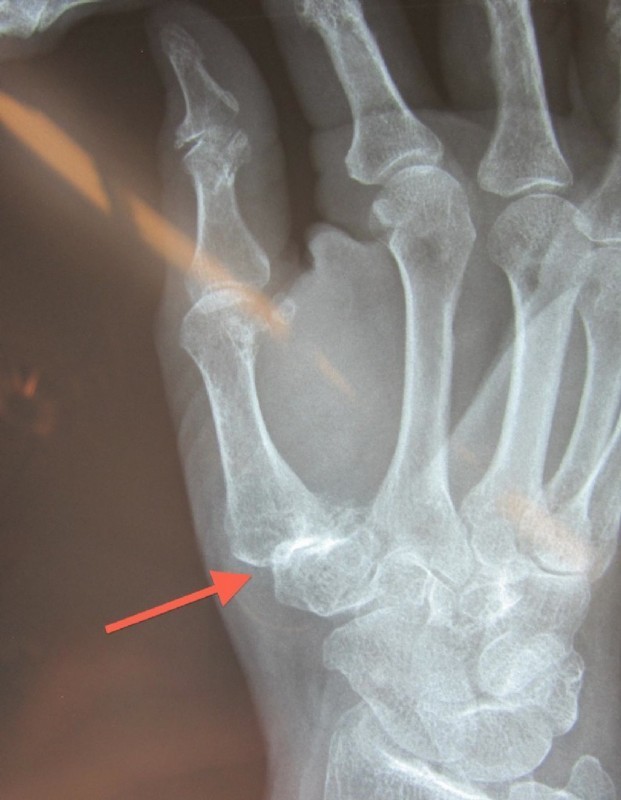

Left: Severe osteoarthritis (abrasion, joint destruction) of the thumb-saddle joint

Middle: Replacement with a hemiarthroplasty pyrocarbon

Right: This patient had, in addition to the thumb-saddle joint osteoarthritis also signs of wear and instability between the wrist bones. She had severe pain and could not use her hand. We reinforced the pyrocarbon endoprosthesis by stiffening three wrist joints. The patient has been symptom-free for over 10 years now and can use her hand without any restrictions.